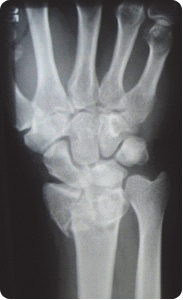

Na radiogramie uwidoczniono

Ilustracja do pytania 3

A. złamanie podstawy I kości śródstopia.

B. paluch koślawy (hallux valgus) stopy prawej.

C. paluch szpotawy(hallux varus) stopy prawej.

D. złamanie guzowatości V kości śródstopia.